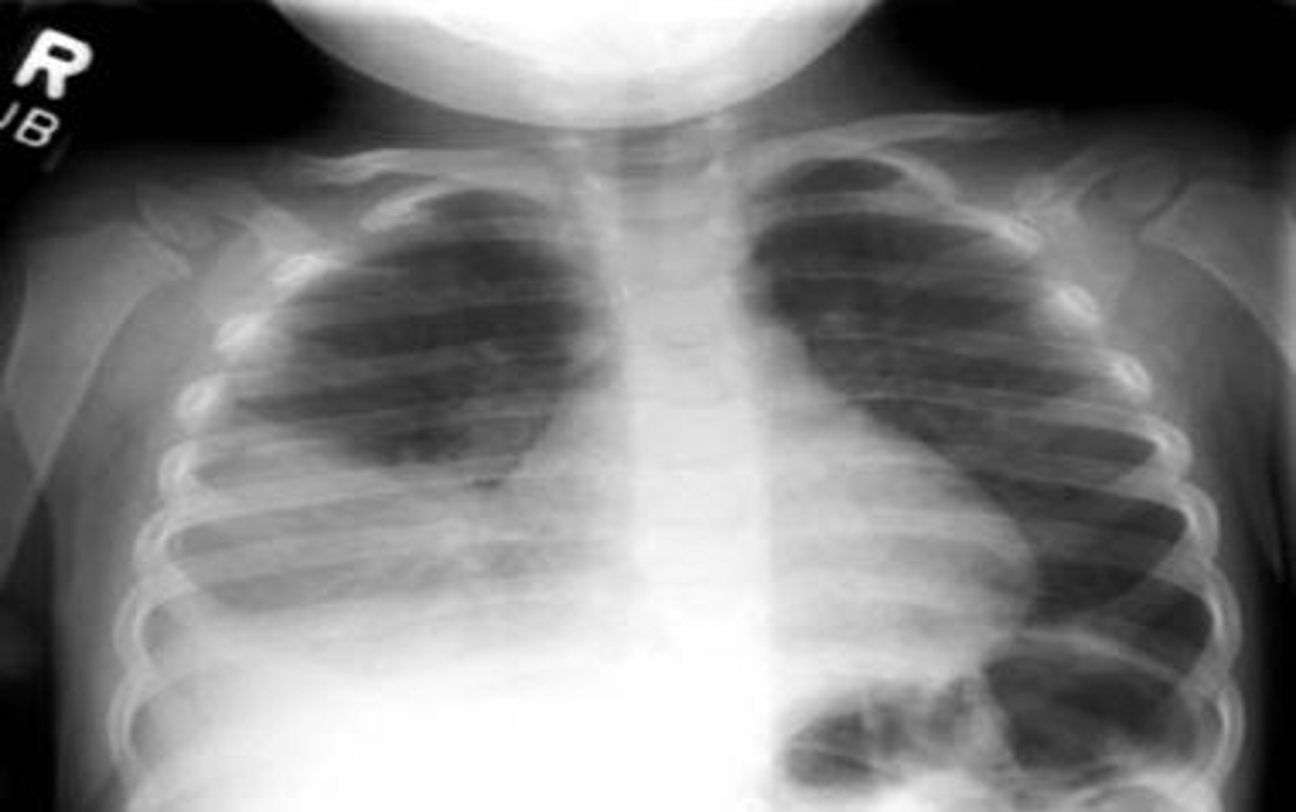

Anteroposterior radiograph from a child with a round pneumonia.

Bronchopneumonia:

- Poorly defined patchy infiltrates scattered throughout the lungs.

- Presence of air bronchograms